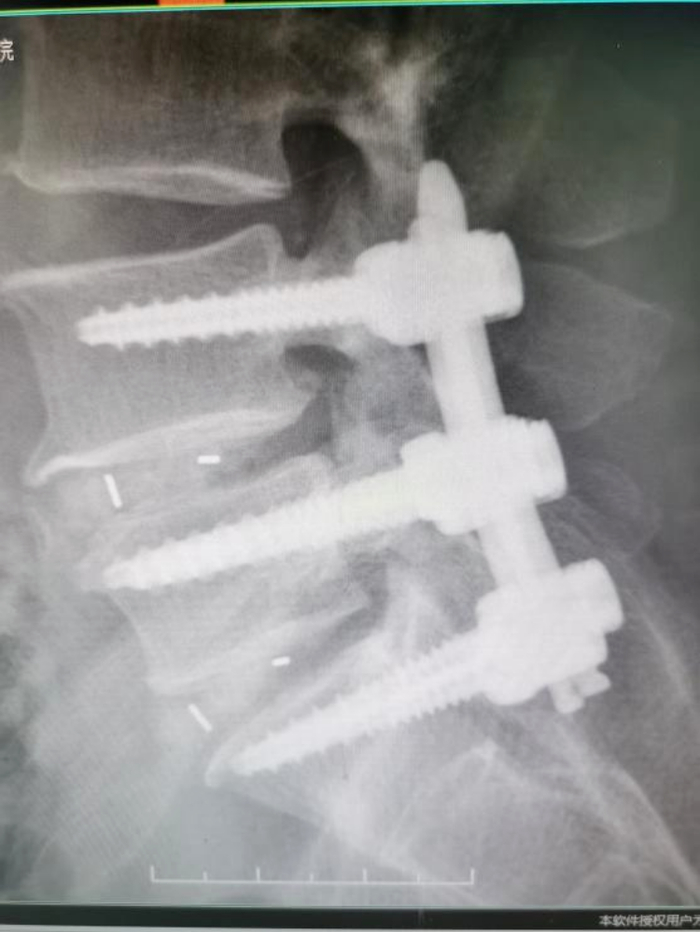

术后腰椎X-ray片提示:内固定位置满意/图源 重医附三院